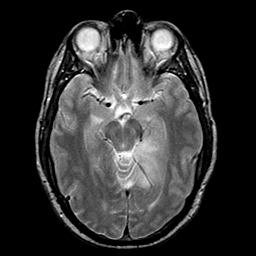

glioma overlay -- Slice #11

[Home][Help][Clinical] Slice 11